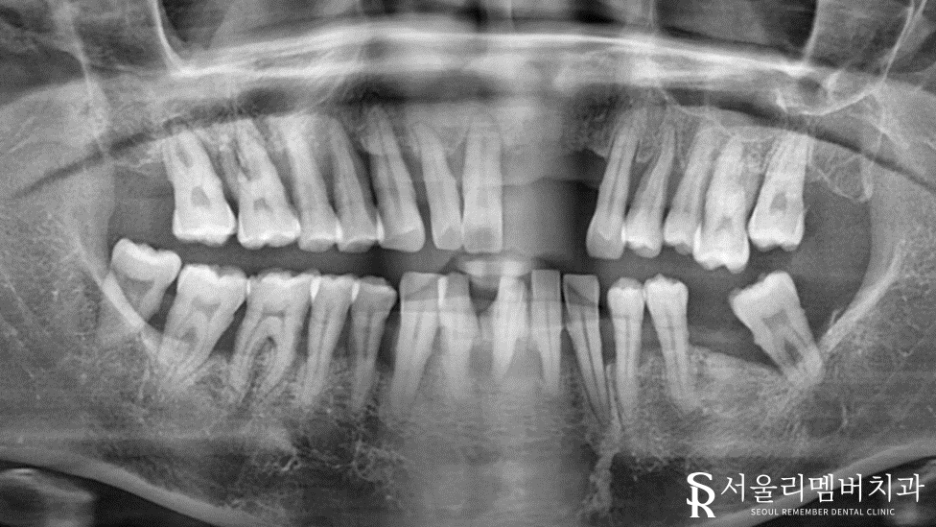

환자께서는 전반적인 치아 통증을 느낀 채 저에게 찾아오셨습니다.

직접 구강 내를 확인해 보니 말씀해 주신 것보다 더! 심각했는데요.

앞니 상실

치경부 드러남

다량의 치석

치주염

충치

여러 문제들이 복합적으로 나타나고 있었습니다.

개인적인 사정으로 인해 진료를 계속해서 미뤄오셨다는데요.

아래 앞니에 쌓여있는 치석을 보면 그 세월을 느낄 수 있죠.

예상컨대 빠져버린 치아들도 잘못된 구강관리(치석 방치 및 잇몸질환)가 원인일 것 같네요.